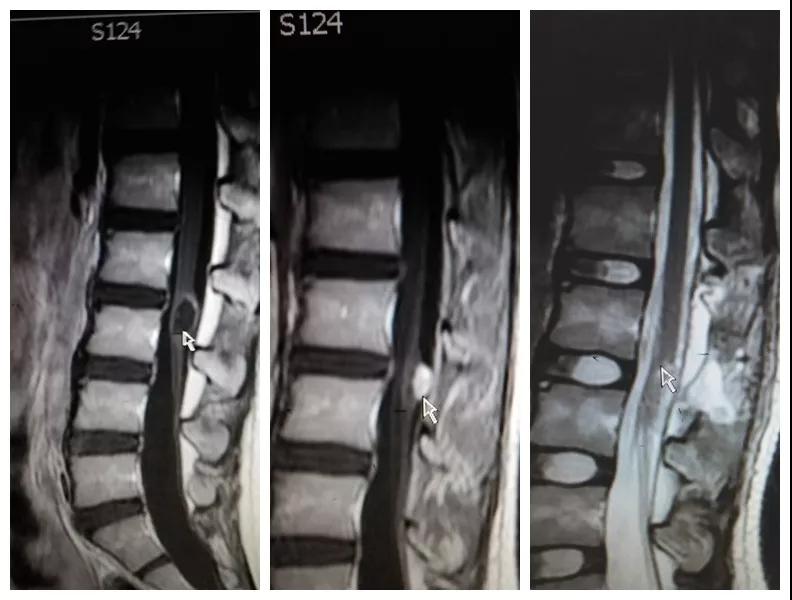

2018年8月,孩子母亲带着一线希望慕名找到按摩视频 神经外科王占尧主任医师。王医生通过详细询问病史、查体、完善相关检查后,明确诊断患者为腰3椎管脊髓内畸胎瘤、硬脊膜外脂肪瘤、脊髓栓系综合症、骶尾部皮毛窦。王占尧耐心与家属沟通病情及手术方式,因手术难度大费用较高患者家属有些犹豫,随后又到西安多家医院咨询,最终选择在中心医院神经外科手术。因患者椎管处有不同部位的四个病变,还伴脊髓内畸胎瘤,分几次手术安全性高但是存在再手术医疗费用高、住院时间长耽误孩子上学等问题,如果选择一次手术切除则存在手术时间长、肿瘤是否能最大限度的全切、污染手术与清洁手术同时进行等系列问题。王占尧主任医师组织医疗团队反复讨论患者病情、斟酌手术方式、评估手术风险、制定详细的手术方案,最终决定在全麻下一次手术为患者同时切除四个病变部位。孩子的父母是一辈子面朝黄土背朝天的农民,面对术前谈话时主管医生提到的种种风险,他们不能完全理解,只是落泪重复:“孩子是我两的希望,我们就把孩子交给你了王大夫!”王占尧正是承受着一旦手术失败,孩子可能原有症状加重、甚至终身大小便失禁、双下肢瘫痪的压力,带着孩子父母沉甸甸的希望走进手术室。

手术很成功。术后孩子恢复非常好,未出现并发症,复查磁共振肿瘤切除干净,大小便失禁症状较术前明显好转,腰部疼痛也得到了缓解,目前已痊愈出院。